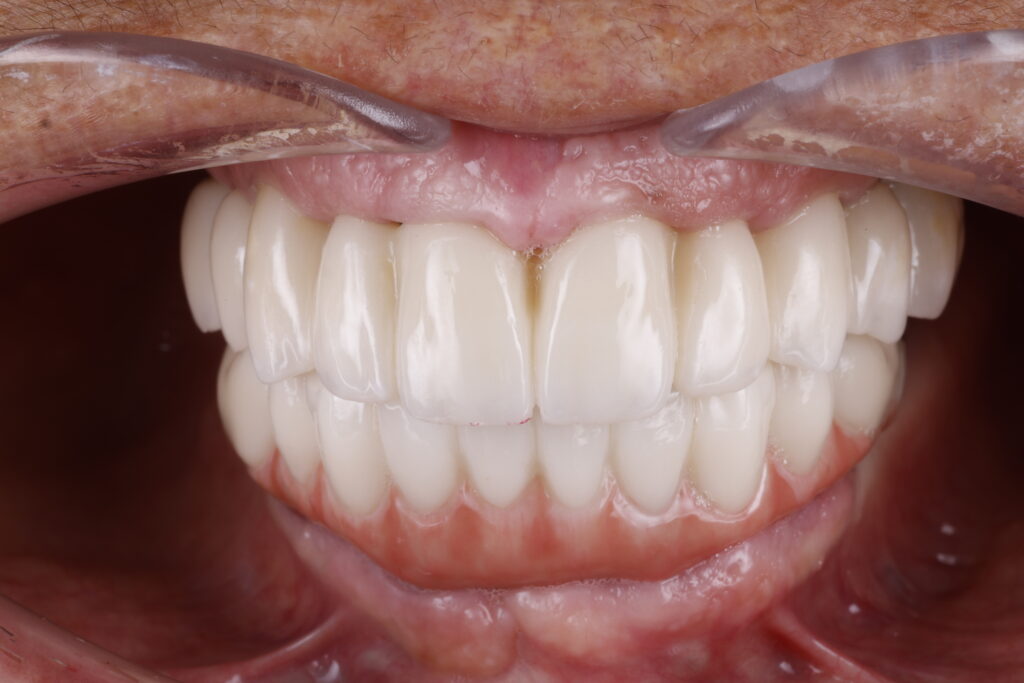

Before

After